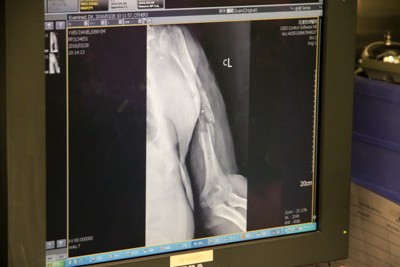

圖說:丹尼爾於三月二十五日抵達花蓮慈濟醫院後,陳英和院長為他拆下已經鬆動的骨外固定器,並做傷口處理。

三月二十六日,丹尼爾抵達花蓮慈院後,陳英和名譽院長為丹尼爾檢查傷口發現,骨折傷口不僅未癒合,加上骨外固定器鬆掉了,只要稍微碰觸到固定器,就會讓丹尼爾疼痛難耐。所以,丹尼爾到院後的第一件事,就是拆下已經鬆動的骨外固定器,傷口做初步處理。減輕固定器痛苦,丹尼爾終於能睡得安穩,他也露出開朗的笑容說:「來到醫院時,愁眉苦臉,現在已經能開懷大笑,人生都改變了!」